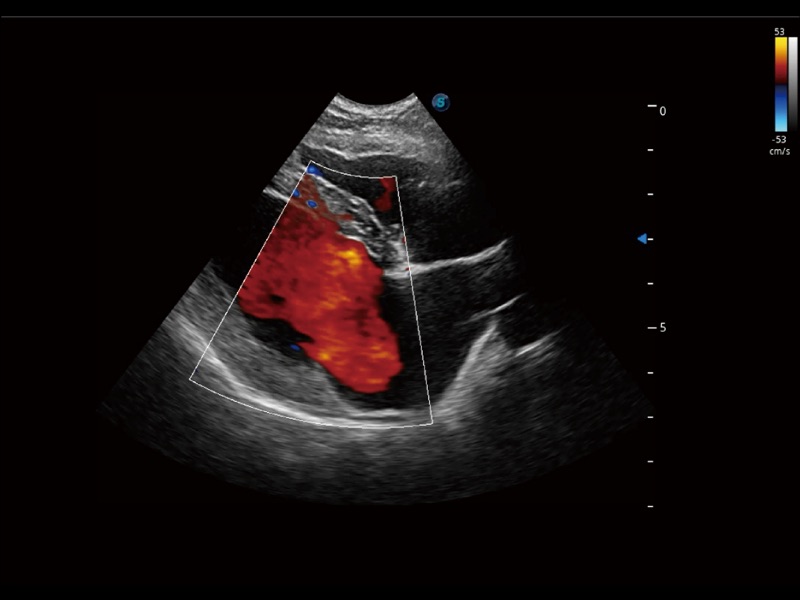

(犬)左室长轴血流

(犬)四腔心